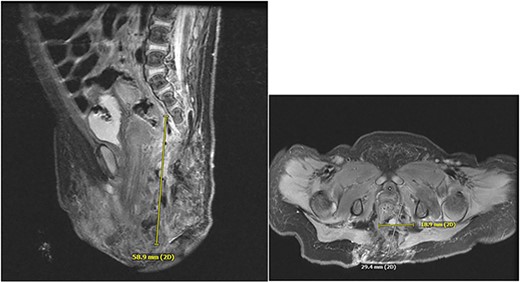

A 3-week-old girl born at 39 weeks, 1 day gestation with a left buttock hemangioma presented to the emergency department with progressive deterioration of the skin of the left buttock, wrapping laterally around the thigh and extending to the labia. She first developed ulceration at 1 week old after receiving silver nitrate treatment for IH at an outside facility. This progressed over 2 weeks to its state upon presentation, involving the left buttock, perianal region, and labia, growing in both size and depth (Fig. 1). On admission, ulceration was managed with broad spectrum IV antibiotics: vancomycin, clindamycin, and cefepime. CT and MRI revealed a 5.9 cm vascular mass with intrapelvic and extrapelvic components and spinal dysraphism from L4 to the sacrum along with spinal cord tethering due to an intradural lipoma, consistent with LUMBAR syndrome (Fig. 2). The patient had involvement on the dorsum of the left foot, consistent with IH (Fig. 3).

Dysmorphic sacrum with rightward curvature. There is an intradural terminal lipoma present along the left aspect of the lower cord, extending from L3-L4 to the caudal thecal sac. Presumed extensive vascular malformation.